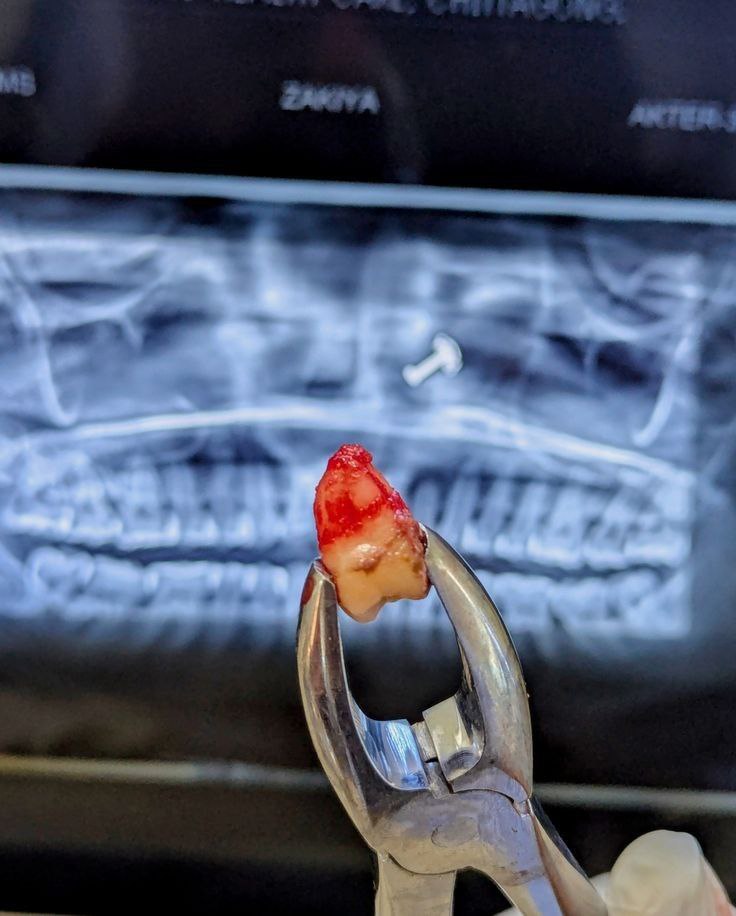

کشیدن دندان: نکات و مراقبت‌های ضروری برای بهبودی سریع

کشیدن دندان عقل و سایر دندان ها